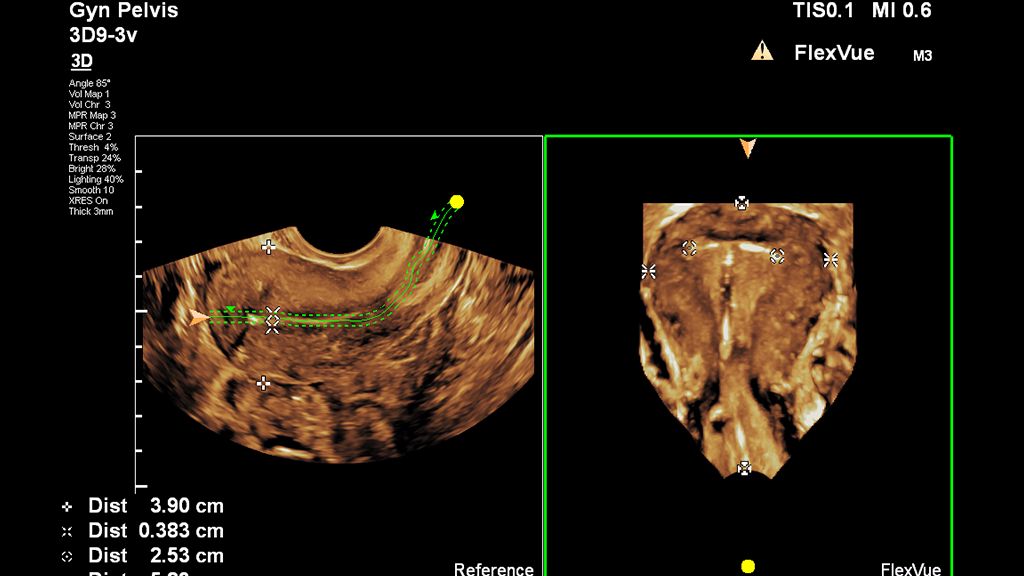

Demonstrated results using FlexVue

It (FlexVue) takes all of the complications out of MPR and manipulation of a surface-rendered volume. By deploying a straight line or a curved trace or continuous trace, we can take a curved image, flatten it out and make it a single planar image.